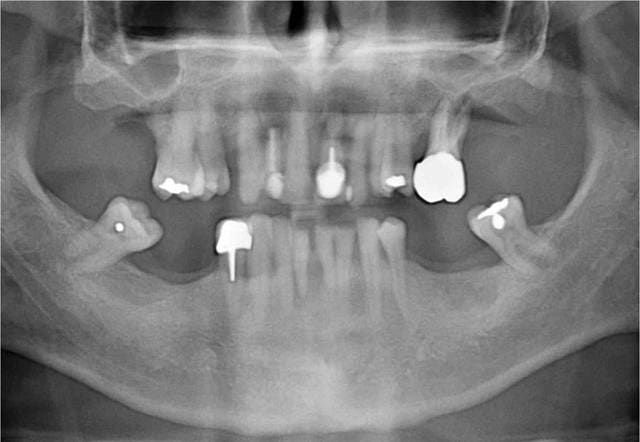

12/10/2015 à 16h31

Votre avis?

Mise en chage imm diate 179 masvfe - Eugenol

Mise en chage imm diate 180 bf9u7f - Eugenol

La patiente est née en 66, je ne sais pas si elle est fumeuse (le tabac n’est pas une contre-indication formelle à la pose d’implant), analyse sanguin ok.

Patiente 57 ans non fumeuse